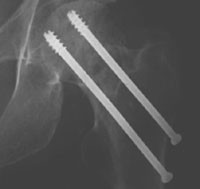

I den første registreringsperioden (gruppe A) ble det brukt to AO Hip Pin, Stratec Medical (fig 1). Dette er kanylerte skruer uten hode. Gjengediameteren er lik skaftdiameteren på 6,5 mm. I den påfølgende registreringsperioden (gruppe B) ble det brukt to AO 7,3 mm Cannulated Screws, Stratec Medical (fig 2). Dette er skruer med hode, gjengediameteren er 7,3 mm og skaftdiameteren 4,5 mm (tab 1).